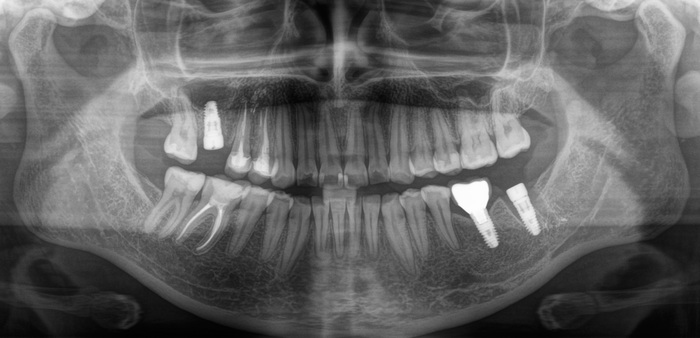

Проходит еще полтора года и пациентка вдруг приходит на осмотр с жалобами на подвижность коронки в области той самой 6ки, с которой мы начали. Сначала показалось, что просто раскрутился винт, фиксирующий коронку к имплантату.

И тут начинается самое интересное. Что такое абатмент мы выяснили из картинки выше, это переходный элемент между коронкой и имлпантатом. Так вот по всем технологиям и нормам он должен быть титановым. Как контрастирует титан на рентгеновском снимке вы можете заметить, посмотрев на имплантат. Видите разницу между 6м и 7м имплантатом?

Так вот абатмент, который вставляется в имплантат из другого материала. Вероятнее всего это кобальт-хромовый сплав. Такие штуки изготавливаются литьевым методом. Все мы знаем, что металл при нагревании расширяется, а остывая сжимается, дает усадку. Соединение имплантат- абатмент должно быть четким. Важны даже микроны. В данном случае наверняка была микроподвижность в этом соединении, высокая нагрузка на винт, в связи с чем он и сломался.

Прикус:

За эти годы ситуация усугубилась, стираемость зубов прогрессировала.